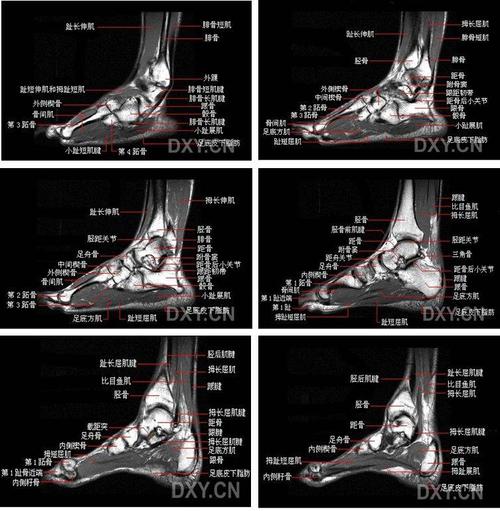

踝关节mri解剖与常见病变,都在这篇文章里!

踝关节mri解剖图谱